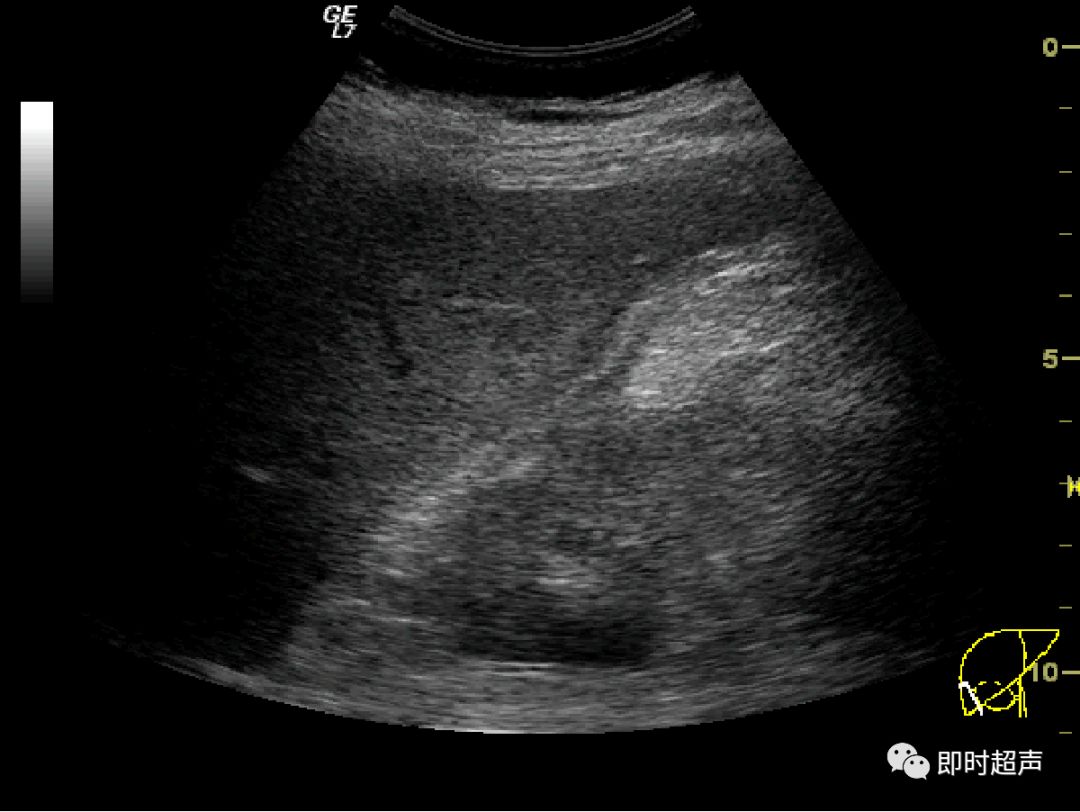

内脏反转超声报告

内脏反转超声报告,内脏反位超声报告模板